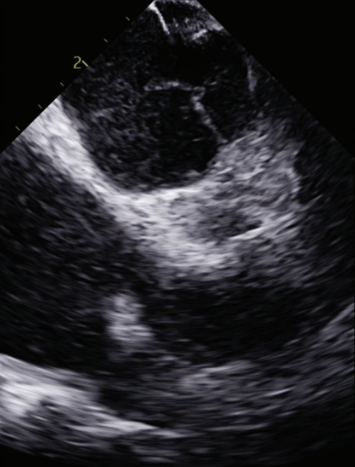

quickly adopted for most cases. The typical workflow for incorporating the 4D ICE catheter involves femoral venous access in the usual manner. To begin a case, the catheter is inserted into the right atrium (RA) and screened for pericardial effusion. Using the V-Plane feature, the LV pericardium can be visualized as well. The catheter is then deflected across the tricuspid valve and into the right ventricular outflow tract. V-Plane through the appendage, in addition to standard 2D imaging, can exclude LAA thrombus (Figure 1). The catheter is withdrawn back to the RA and imaging of the interatrial septum is obtained to help guide transseptal puncture in the usual manner. Once puncture is completed, the septum is flossed with the transseptal sheath. The sheath is then pulled back to the inferior vena cava (IVC). The ICE catheter is then withdrawn to the low RA with direct visualization of the wire as it crosses the septum. Under ultrasound and fluoroscopic guidance, the ICE catheter is pushed across the septum into the mid LA. The delivery sheath is then pushed across the puncture site into the LA. The ICE catheter can be positioned in different locations throughout the LA; however, placement along the mitral annulus frequently allows adequate visualization of the LAA (Figure 2). Multiplanar imaging of the LAA allows for device sizing and selection (Figure 3). Once a device size is selected, the implant is prepped and delivered using multiplanar and fluoroscopic imaging. During sheath manipulation and device delivery, the sonographer can make fine adjustments to the image to maintain adequate visualization so the operator can focus on device delivery. Once an implant is delivered, confirmation of position and occlusion can easily be performed by color flow Doppler and 2D/3D imaging (Figure 4). At the end of the procedure, a quick survey can exclude pericardial effusion.